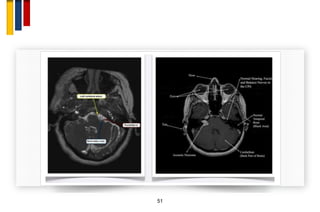

Hemifacial spasm

50

• Work Up

– MRI of cerebellopontine angle to R/O tumor

51